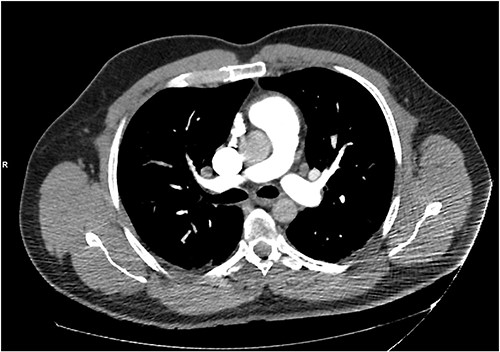

He presented with right sided abdominal pain associated with jaundice, fever, myalgia and arthralgia after receiving his second dose of the penultimate cycle of intra-renal BCG instillation. He did not have any tuberculosis contacts. His parameters on admission were stable. C-reactive protein levels were 230 mg/l and white cell count (WCC) was 6.51 × 109/l. His liver function tests were deranged, with a mixed obstructive and hepatitic picture. A CT kidneys, ureters and bladder (KUB) showed mild diffuse dilatation of the right ureter and renal pelvis with minimal amount of peri-ureteric fat stranding (Fig. 1). A CT scan of the abdomen with intravenous contrast (IV) was performed, this showed a distended right ureter down to the vesicoureteric junction, peri-ureteric fat stranding and lymphadenopathy in the aorto-caval space together with splenomegaly and atelectatic changes (Fig. 2).

An initial CT KUB showed mild diffuse dilatation of the right renal pelvis (as indicated by the arrow).